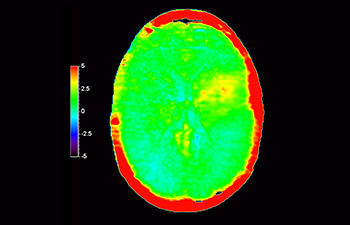

Recidiva del glioblastoma

Imágenes cerebrales de recidiva del glioblastoma

con 3D APT